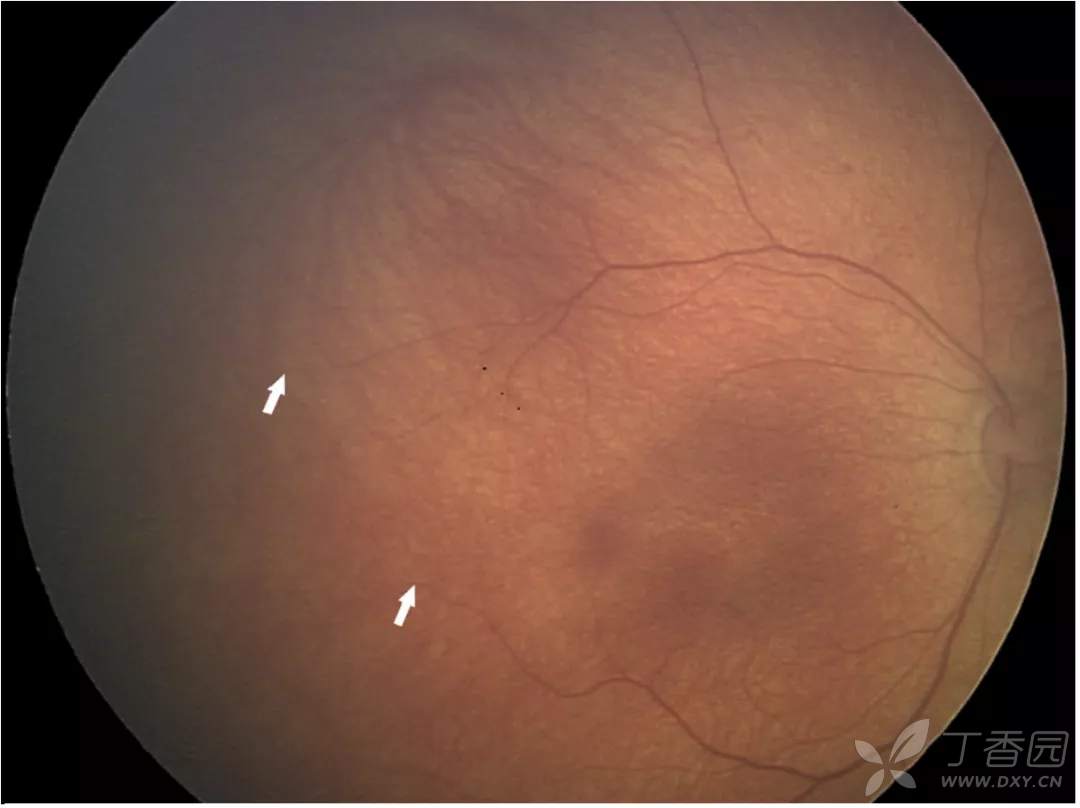

ROP 1至3期OCT图像

图. OCT图像上的1期分界线(白箭)与视网膜血管-无血管连接处对齐。

图. OCT图像上的2期脊(白箭)表现为视网膜内层局灶性增厚、隆起,与en face图像上血管区-无血管区交界处较宽的暗边界一致。

图. OCT图像和en-face图像显示3期视网膜外新生血管形成(白箭)。